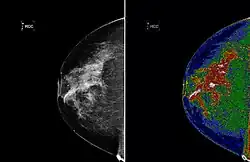

The left image shows an original mammogram before MED-SEG processing. The image on the right, with region of interest (white) labeled, shows a mammogram after MED-SEG processing.